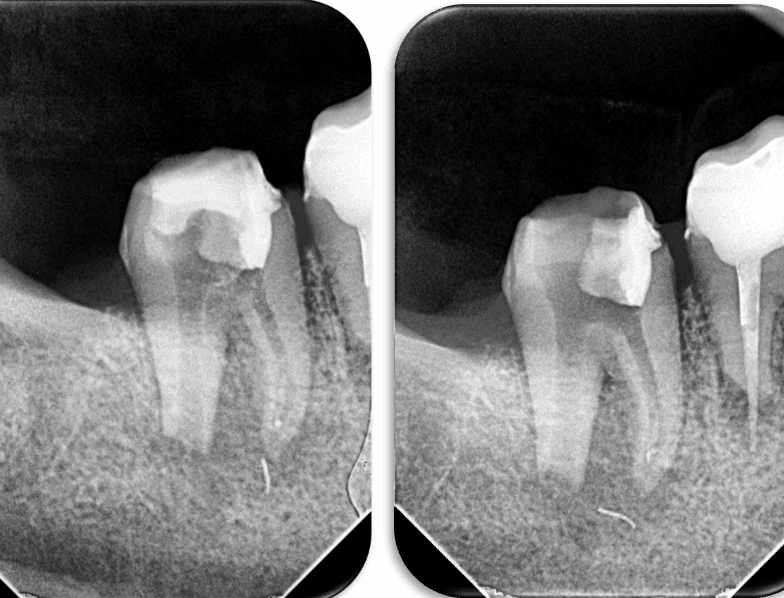

29 yaşındaki sağlıklı erkek hasta kök kanalındaki kırık eğe nedeni ile kliniğimize başvurdu. Yapılan radyografik muayenede distal kanalda apikalden taşkın guta ve kırık alet olduğu tespit edildi (RESİM 1).

RESİM 1: Apikalden taşkın eğe ve guta